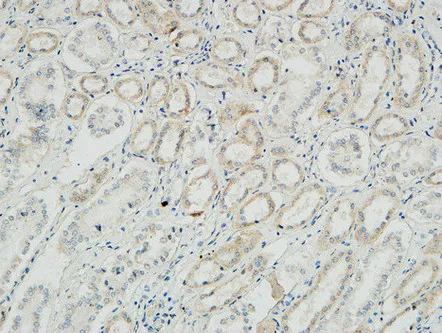

Na+/K+-ATPase α1 Rabbit Polyclonal Antibody

Cat: APRab14378

Size1:50μl Price1:$118

Size2:100μl Price2:$220

Size3:500μl Price3:$980

Size2:100μl Price2:$220

Size3:500μl Price3:$980